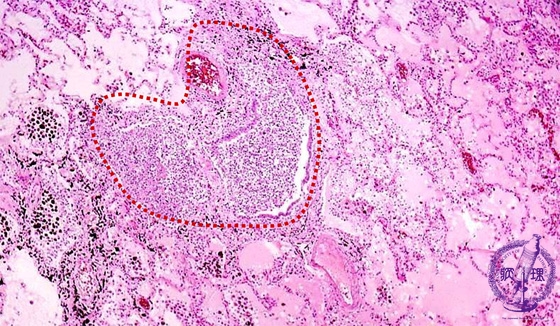

- ★(7)Bacterial pneumonia (bronchopneumonia)

Microscopic view (HE stain, low power view): The bronchiole is filled with purulent debris and surrounded by edema and an inflammatory infiltrate. Bronchial structure is obscured due to destruction of bronchial alveoli (dotted line).